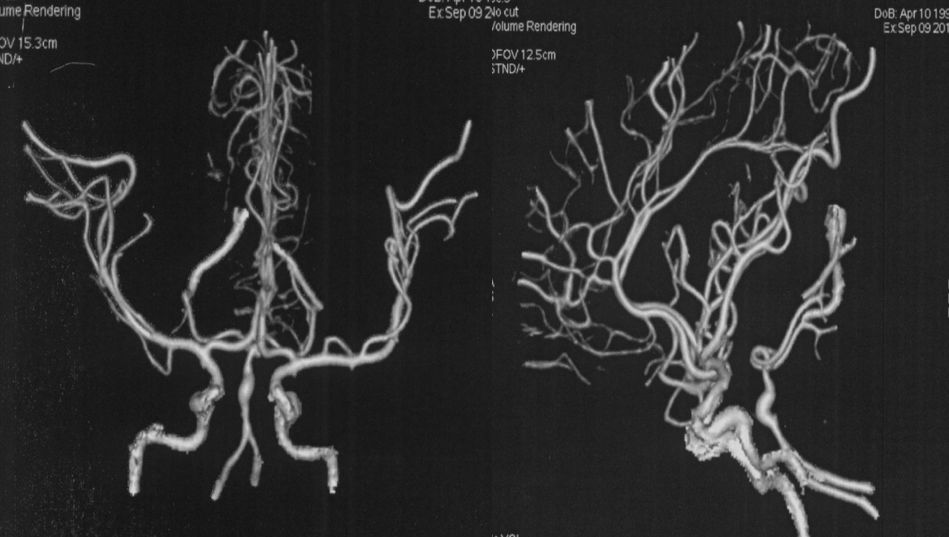

当地医院 CTA:基底动脉中上段瘤样扩张(图2)。

图2

当地医院DSA:基底动脉中上段夹层动脉瘤(2019-09-10)(图3)。

图3